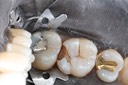

Bryan Sato #2 amalgam removal

Bryan Sato #2 prep